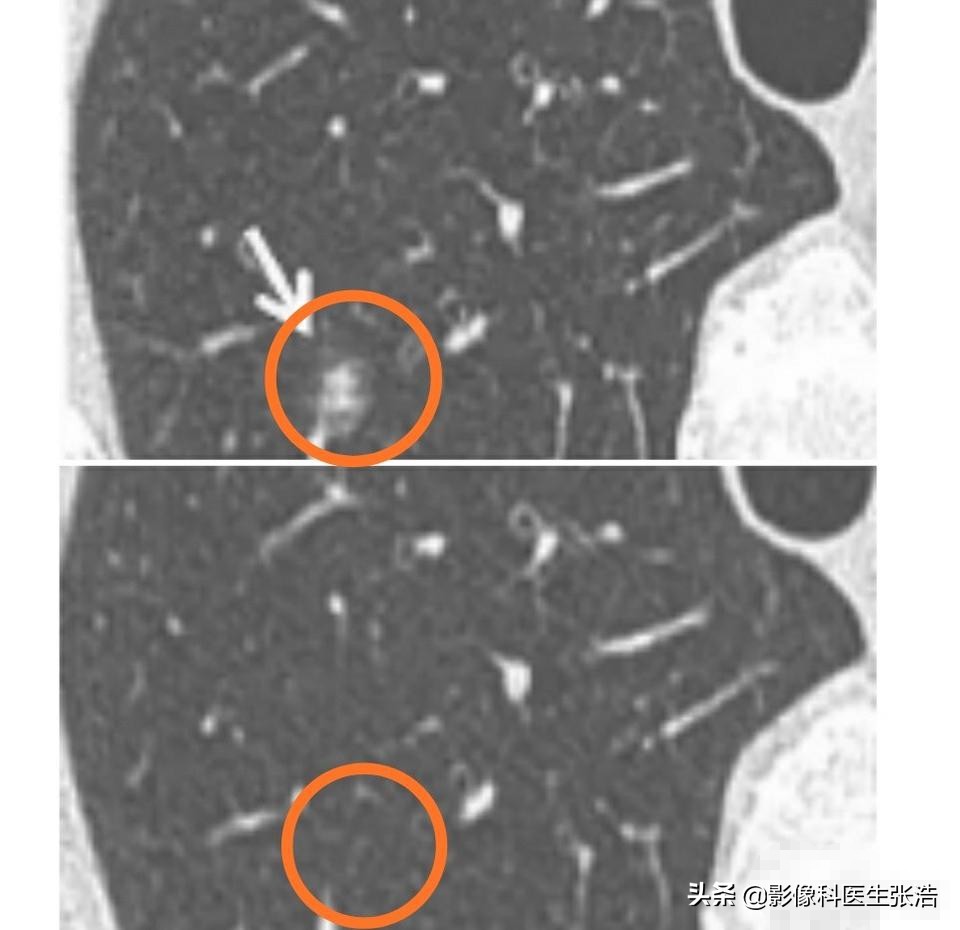

4、血管集束征,因为需要不断的吸取营养,往往会牵拉周围小血管,甚至出现自给自足的新生小血管!下图就是一个典型的恶性磨玻璃结节,大家能看到它的恶性征象吗?